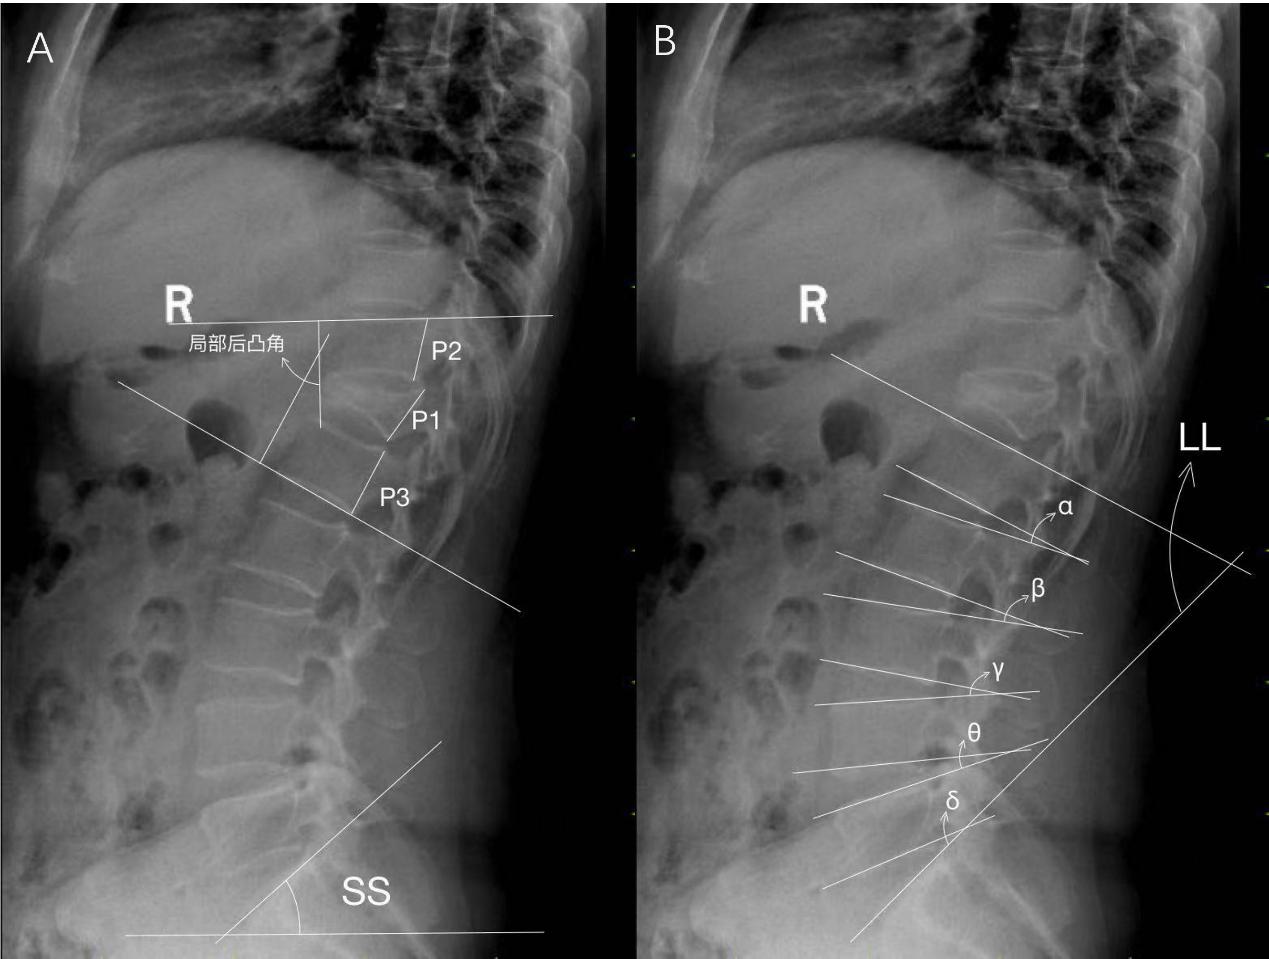

Impact of disease duration on lumbar curvature correction in patients with rigid post-traumatic thoracolumbar kyphosis

Yang Junjie, Zhang Hao, Chen Zhike, Chen Yao, Jia Bingxu, Wang Qing, Li Guangzhou, Wang Gaoju

BACKGROUND: Currently, most studies on rigid post-traumatic thoracolumbar kyphosis focus on overall sagittal balance and surgical intervention, while the effect of the disease duration on the change of lumbar compensatory curvature and degeneration is still unclear.

OBJECTIVE: To explore the effect of the disease duration on lumbar degeneration and the potential mechanism of rigid post-traumatic thoracolumbar kyphosis in patients with rigid post-traumatic thoracolumbar kyphosis, and provide a basis for optimizing treatment strategies.

METHODS: Clinical and imaging data from 79 rigid post-traumatic thoracolumbar kyphosis patients were retrospectively analyzed. The patients were divided into two groups according to the disease duration: Patients with a disease duration of ≤ 5 years were categorized as group A (n=40), and those with > 5 years as group B (n=39). X-ray images were used to measure the local kyphosis angle of the injured vertebra, the height of the posterior walls of the injured vertebra and adjacent vertebrae, lumbar lordosis, the intervertebral space angle for each lumbar segment, and sacral slope. The Weishaupt-CT classification system was employed to assess lumbar facet joint degeneration. Pfirrmann-MRI grading system was applied to evaluate disc degeneration. The visual analog scale for back pain, Oswestry Disability Index, SRS-22 and American Spinal Injury Association spinal injury grading were compared between the groups. The impact of disease duration on clinical symptoms and imaging characteristics of patients with rigid post-traumatic thoracolumbar kyphosis was analyzed.

RESULTS AND CONCLUSION: (1) There were no significant differences in age, gender, visual analog scale scores, fracture location, fracture type, or American Spinal Injury Association grading between the two groups (P > 0.05). Group A had a significantly higher SRS-22 score than group B (P < 0.05); Group B had a significantly higher Oswestry Disability Index score than group A (P < 0.05). (2) Group B had a substantially greater kyphosis angle of the injured vertebra, lumbar lordosis, and L4/5 intervertebral space angle than group A (P < 0.05). (3) There were no significant differences between groups A and B in the L1/2, L2/3, L3/4, or L5/S1 intervertebral space angles or sacral slope (P > 0.05). (4) Group B showed significantly greater facet joint degeneration at the L3/4, L4/5, and L5/S1 segments and significantly greater disc degeneration at the L2/3, L3/4, L4/5, and L5/S1 segments compared with group A (both P < 0.05). (5) Pearson correlation analysis indicated a positive correlation between disease duration and both the local kyphosis angle of the injured vertebra and lumbar lordosis in group B (r=0.335, 0.418, P < 0.05). (6) Over time,  rigid post-traumatic thoracolumbar kyphosis patients experience increased lumbar lordosis and accelerated lumbar degeneration, with the L4/5 segment playing a primary role in compensatory lumbar curvature. Surgical correction should focus on adjusting the lower lumbar curvature.

Figures and Tables | References | Related Articles | Metrics